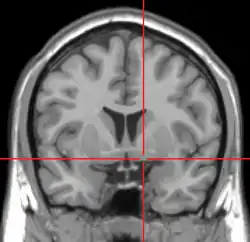

Coronal MRI slice with cross-hairs indicating location of the substantia innominata